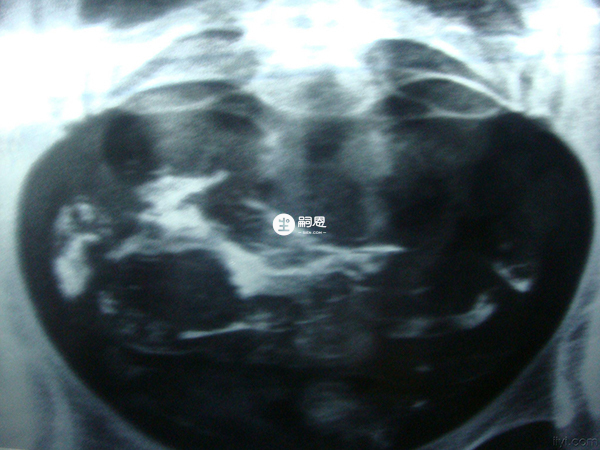

子宫输卵管造影是判断输卵管疏通与否的一种检查方法,包括输卵管造影在内,关于输卵管检查的几种类型还有输卵管通液、超声检查、腹腔镜检查、输卵管通气试验等,以上这些都是针对女性输卵管是否正常的一些检查方法。

整个输卵管造影流程下来,对女性身体的伤害较小,同时在有经验的医验操作下准确率高达98%,输卵管造影相比宫腔镜、腹腔镜、输卵管镜等检查来说,在许多方面是无法替代的,下面来看看详细的输卵管造影过程。